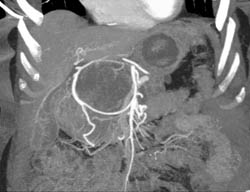

Diagnosis

Cystadenoma